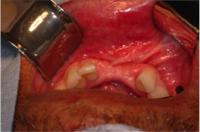

2.

Grid mesh

was used to contain

mp3

.

Photo shows the area exposed after 4 months.